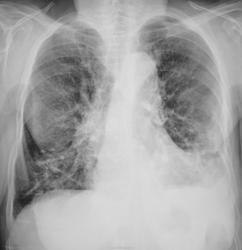

С подозрением на пневмонию направлена на рентгенографию ОГК.

Честно говоря, свежей инфильтрации не вижу. Легкие фиброзны, слева передне-базальные синусы облитерированы.

Возраст большой. Изменения сосудов в виде варикозных расширений, фиброз. В левом лёгком ,наверное, изменения в виде фиброза за счёт мелких тромбоэмболий. С сердцем проблем нет?

Согласна с фиброзными изменеиями и усиленным с/рисунком, структура корней нечеткая. И видится мне над куполом слева (в прямой проекции на фоне сердечной тени) газовый пузырь. Дала бы глоток бария.